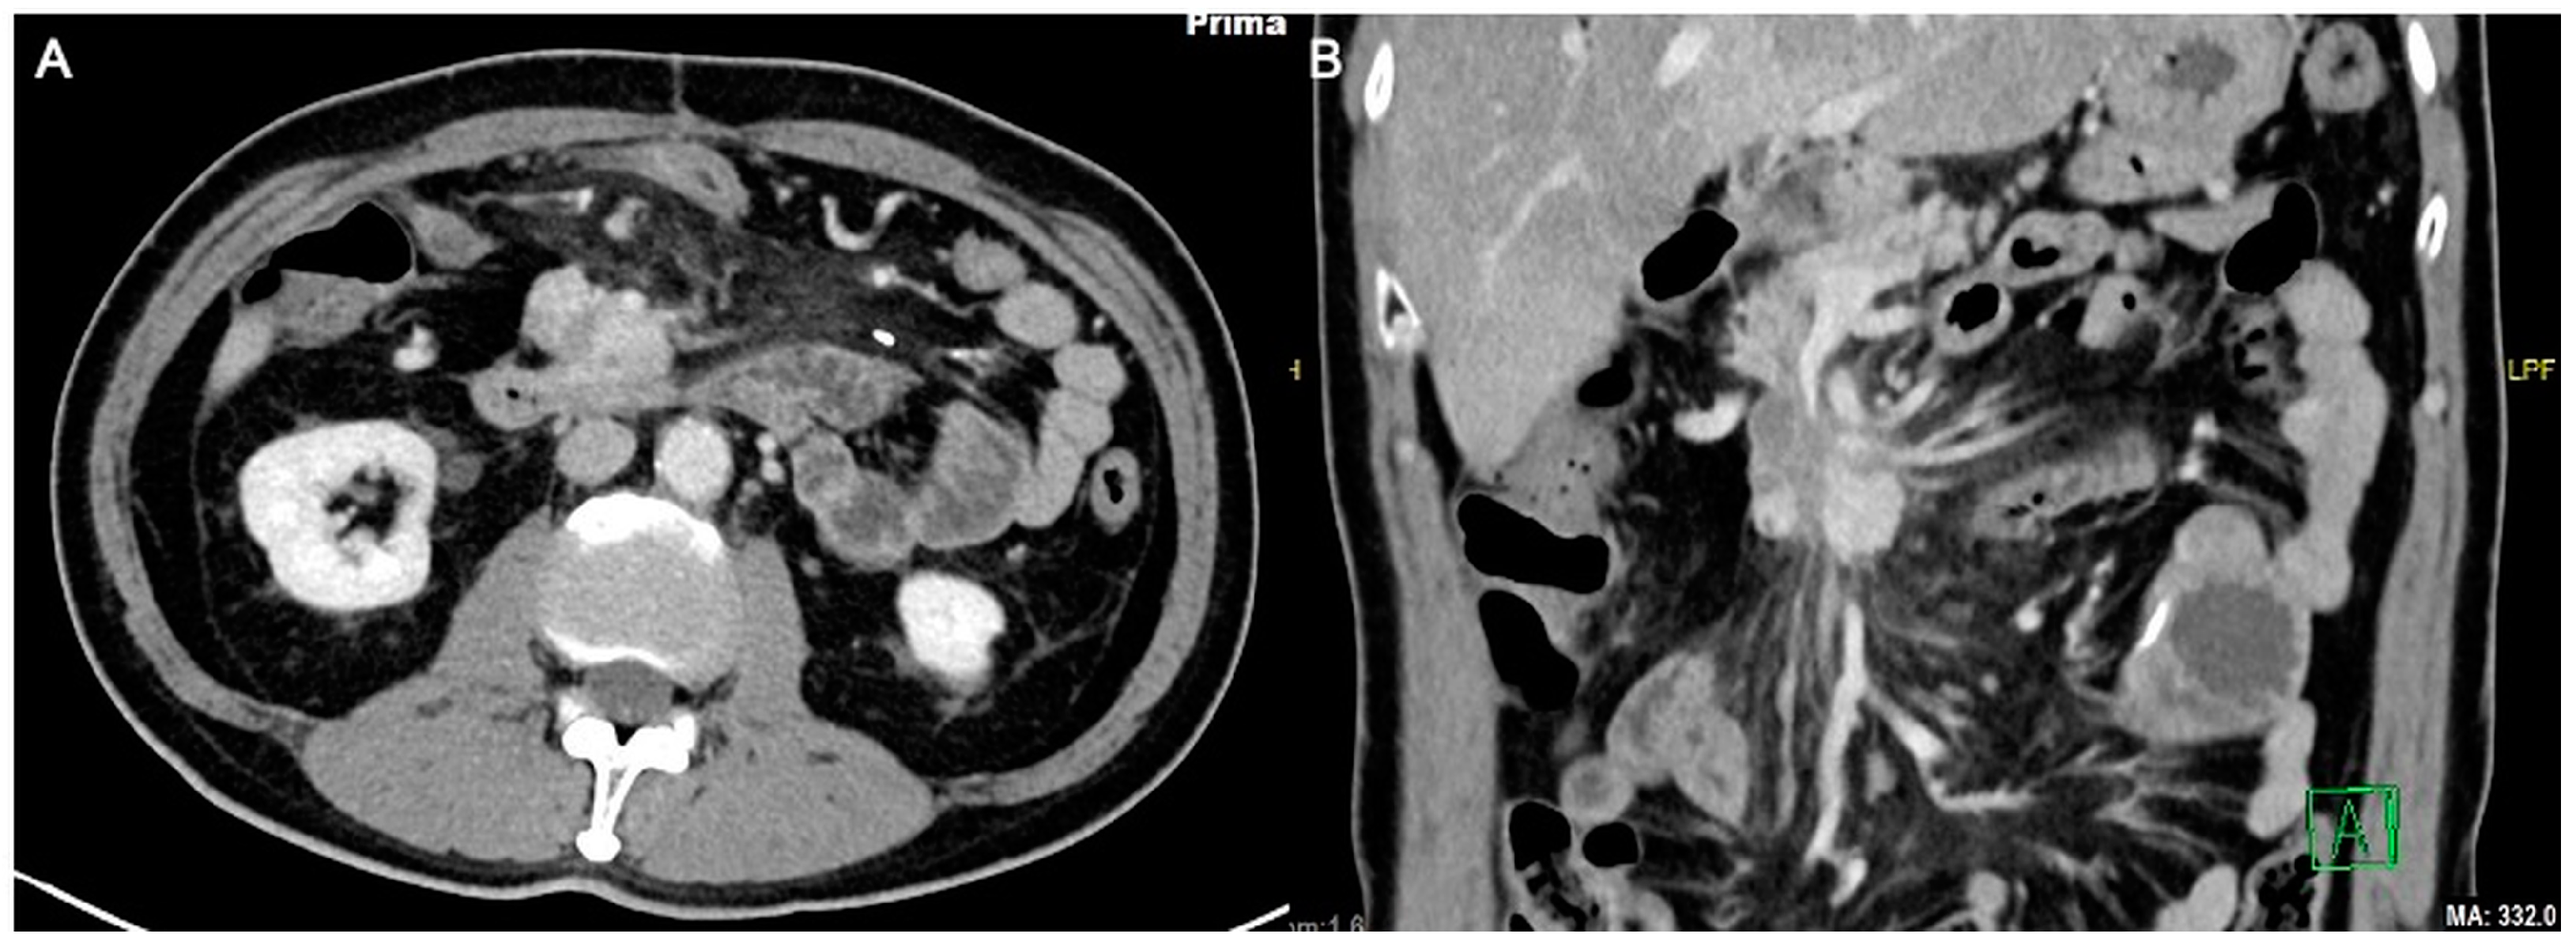

Figure 4.

Axial (A) and coronal (B) computed tomography images 1 year post open irreversible electroporation. The pancreatic mass now measures approximately 3.9 × 2.6 cm.